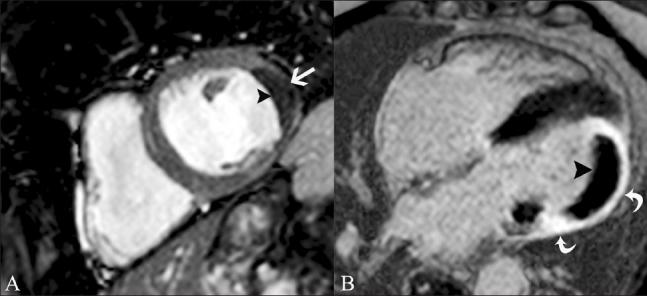

磁共振成像在评估心电图ST段抬高患者中的应用价值。

Utility of magnetic resonance imaging in the evaluation of patients with ST segment elevation on an electrocardiogram.

ST segment elevation is an important electrocardiographic (ECG) change that is typically found in acute myocardial infarction, but may also be seen in a variety of other conditions. MRI plays an important role in the evaluation of these patients. MRI not only establishes the diagnosis, which is essential for appropriate management, but also helps in the assessment of other factors that are important for risk stratification. In this review, we discuss the common and uncommon causes of ST segment elevation and the role of MRI in the evaluation of these disease processes.

摘要